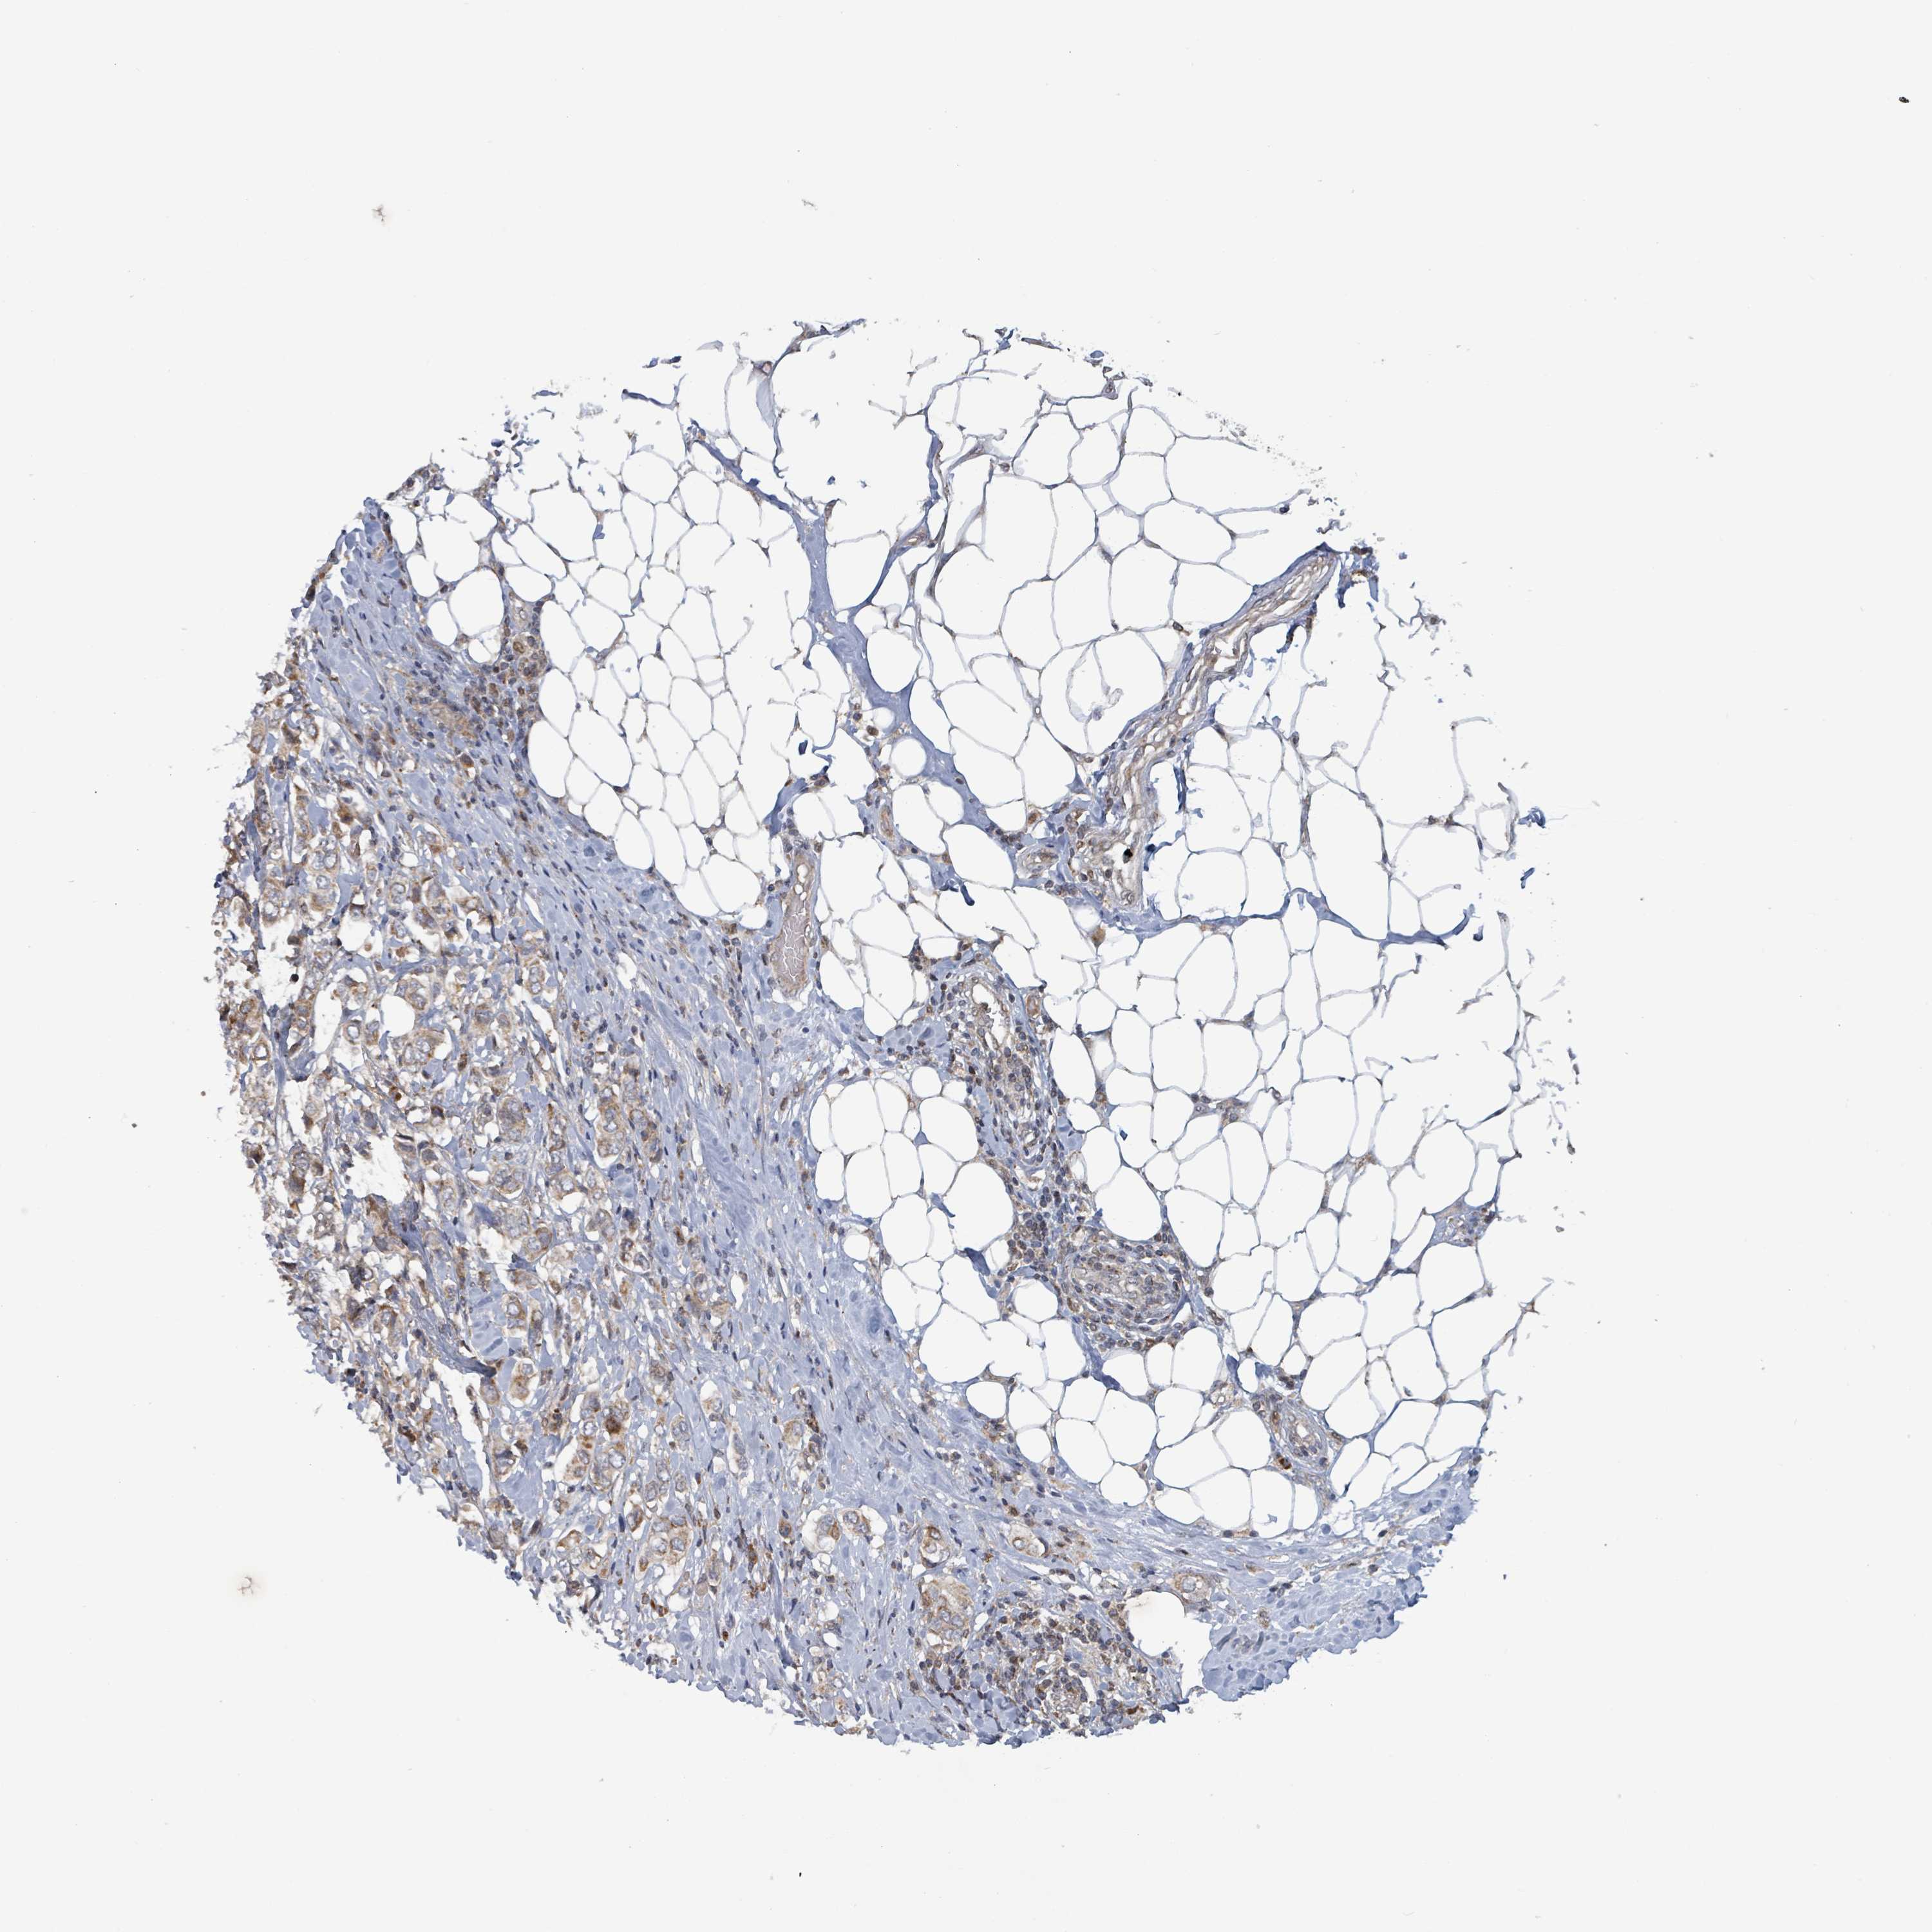

BRCA TCGA BRCA VALIDATION PROTEIN EXPRESSION